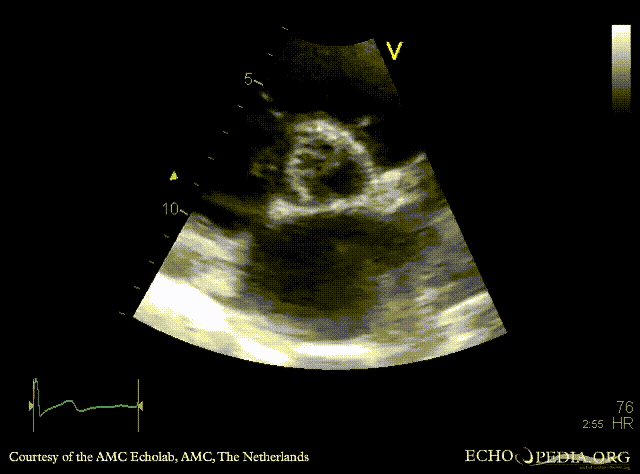

PLAX: vegetations on aortic valve, dilated left ventricle and left atrium PLAX: Color Doppler, severe aortic regurgitation, excentric jet, and moderate mitral regurgitation